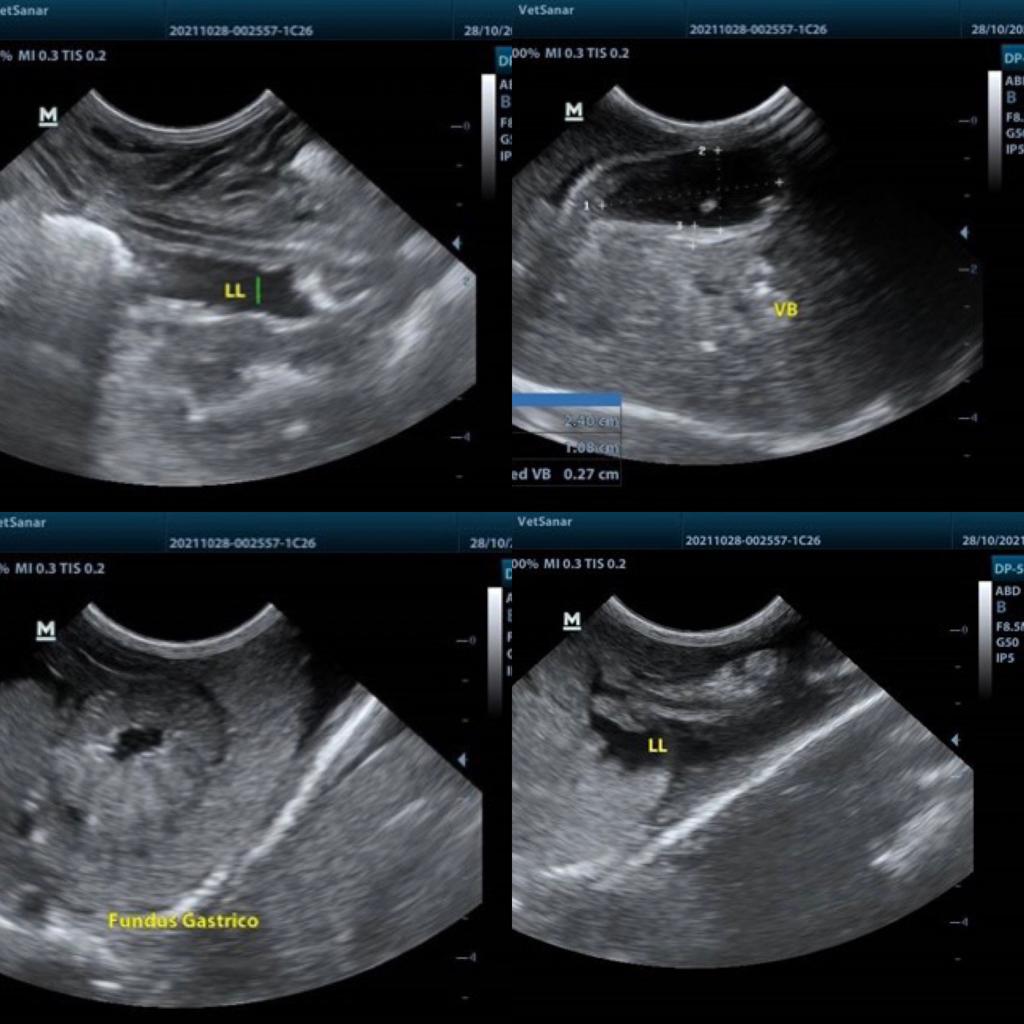

Lupita fue encontrada por su cuidadora abandonada con sus hermanitos botada dentro de una lona. Llega a consulta de un mes de edad, porque les preocupa que tiene su barriguita muy distendida. Quieren consultar otra opinión por ser una cachorrita tan pequeña quieren un manejo mas holístico. Tomamos una ecografía y realizamos exámenes de química sanguínea y encontramos su hígado en falla, vesícula biliar, estomago e intestino muy afectados inflamados, liquido abdominal libre en su abdomen por lo cual se ve tan abultada. El pronostico en estos cachorritos es reservado ya que algunos medicamentos usados por la medicina convencional no son fácilmente metabolizados por su hígado inmaduro y en este caso mas complicado aun ya que su hígado se encontraba muy enfermo. Gracias a las terapias no convencionales realizadas sin efectos secundarios en una cachorrita tan pequeña, al compromiso de su cuidadora quien fue muy puntual con sus tratamientos ya que estos medicamentos requieren altas frecuencias de administración.

EVOLUCION: Lupita tuvo una excelente evolución en su control ecográfico a las 2 semanas de tratamiento ya no tenia liquido libre, ya no tenia anemia. Seguía eliminando muchos parásitos a pesar de varias desparasitaciones realizadas por lo cual fue necesario un acompañamiento de sus defensas para poder vacunarla pero ahora es una perrita sana y feliz.

Ecografía

Según los resultados de ecografía el tamaño del abdomen de Lupita se debía a gran cantidad de liquido libre porque su hígado estaba fallando.